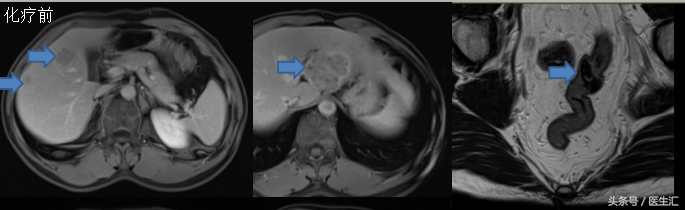

影像学资料:

肝脏、盆腔MRI:乙状结肠癌,侵犯肌层,未明显突破浆膜面,局部系膜小淋巴结显示,肝脏多发转移瘤,较大者位于左叶Ⅲ段,肝脏Ⅳ、Ⅷ血管瘤。

化疗前